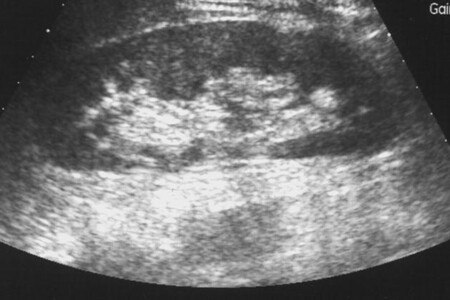

Cysta ledvin, neboli cystická choroba ledvin je závažná vrozená vada. Jde o mnohočetný výskyt cyst v ledvině, které mohou dosahovat až čtyř centimetrů. Toto onemocnění dělíme na autozomálně dominantní a autozomálně recesivní cystickou chorobu ledvin. V čem se liší a jaké z těchto dvou má příznivější prognózu?